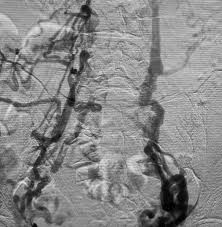

Interventional Radiology Clot Busting Treatment Prevents